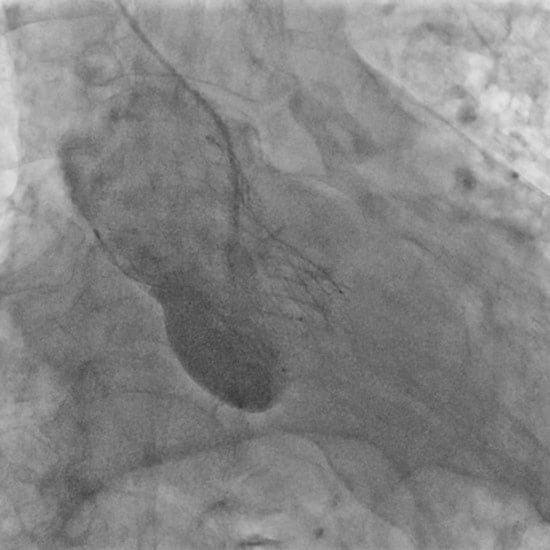

A 34-mm Evolut transcatheter aortic valve (TAV) (Medtronic) was deployed with a good result (Figure 1G). Closure of the femoral access site was uneventful (Figure 1H).

Figure 1G: Implantation of self-expanding transcatheter aortic valve.

Figure 1H: Femoral angiogram demonstrated successful percutaneous closure.